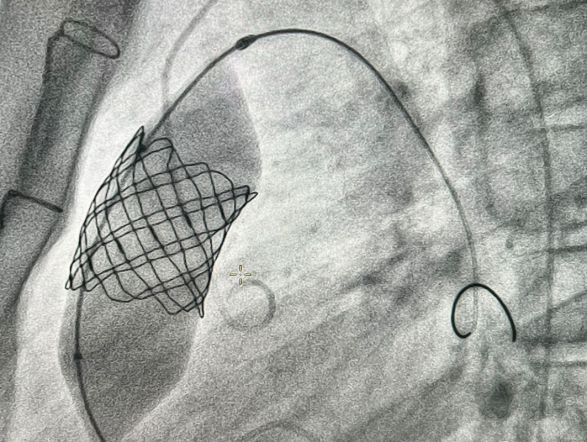

У пациента из Луганской Народной Республики просвет ранее имплантированного кондуита составлял 1,5 сантиметра, поэтому рентгенхирурги на первом этапе расширили его методом баллонной дилатации. При этом был риск разрыва сосуда, поэтому, чтобы избежать возможных осложнений, медики сначала имплантировали стентграфт – металлический каркас, покрытый герметичным полимером. Просвет кондуита удалось расширить до необходимого диаметра. Затем через бедренную вену хирурги доставили к сердцу искусственный биологический клапан лёгочной артерии Myval индийского производства.

Сложную операцию провела команда врачей Педиатрического университета - рентгенэндоваскулярные хирурги Михаил Комиссаров, Владимир Приворотский и Иван Алешин. Неоценимую помощь медикам СПбГПМУ оказал заведующий отделением рентгенэндоваскулярных методов диагностики и лечения Городской многопрофильной больницы №2 Евгений Шлойдо.